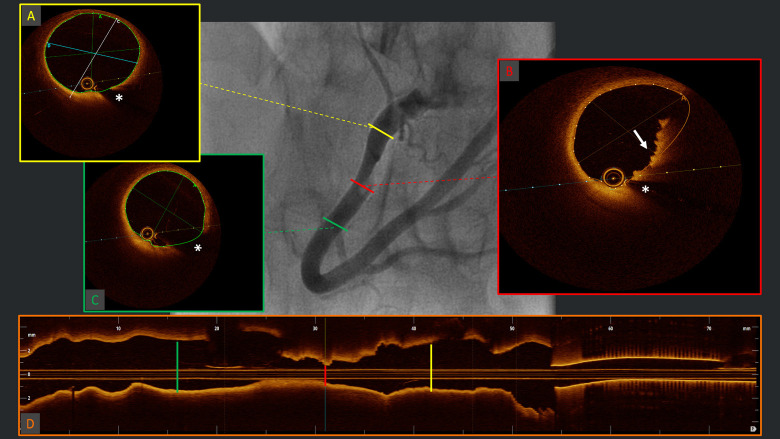

Abstract Image